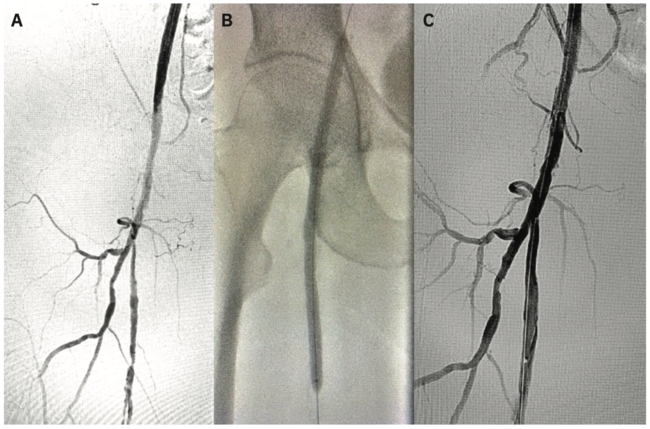

Access was obtained in the right radial artery with ultrasound guidance, and a 6 French (Fr) Glidesheath Slender (Terumo Interventional Systems) was placed. A standard radial cocktail was administered. Over an .035-inch J-wire, a 4 Fr 150 cm Glidecath Multicurve (Terumo Interventional Systems) with side holes was advanced into the distal abdominal aorta. Iliac angiography was performed. A 400 cm angled .035-inch Glidewire (Terumo Interventional Systems) was then used over the Glidecath to selectively cannulate the right popliteal and external iliac arteries for infrapopliteal and femoral arterial angiography, respectively, followed by the left popliteal and external iliac arteries. Digital subtraction images demonstrated severe proximal to mid SFA disease in the right leg with 3-vessel runoff (Figure 1A), and severe disease of the left leg up to the mid SFA, with 3-vessel runoff. (Figure 2A). Pressure gradients were measured on pullback from the popliteal artery to the common femoral arteries, confirming hemodynamic significance of the lesions. At this time, we proceeded with transradial endovascular intervention of the bilateral femoropopliteal arteries.

The Glidecath was removed. Heparin was administered to therapeutic activated clotting time (ACT). Over the .035-inch Glidewire, the Glidesheath Slender was removed and replaced with a 6 Fr 119 cm R2P Destination Slender Guiding Sheath (Terumo Interventional Systems), which was advanced to the level of the left common external iliac artery. An .018-inch 335 cm ViperWire (CSI) was taken to the infrapopliteal arteries. The entire left SFA into the moderately diseased proximal left popliteal artery was ballooned with a 5 mm x 200 mm Metacross balloon (Terumo Interventional Systems), followed by drug-coated balloon (DCB) angioplasty in the proximal to mid SFA with a 6 mm x 150 mm IN.PACT 018 DCB (Medtronic) (Figure 2B). The IN.PACT 018 DCB has only recently become available in the U.S. in a 200 cm shaft length on an .018-inch platform, facilitating femoropopliteal treatment from the transradial approach. Following left leg intervention, the .018-inch wire was removed, and the sheath was pulled back over the .035-inch Glidewire, and then advanced over the dilator into the right external iliac artery. The proximal to mid right SFA was similarly treated with a 5 mm x 200 mm Metacross balloon, followed by DCB with a 6 mm x 150 mm IN.PACT 018 (Figure 1B). Final angiograms of both legs showed no significant residual stenosis or flow-limiting dissections (Figures 1C and 2C), with 2+ distal pulses.